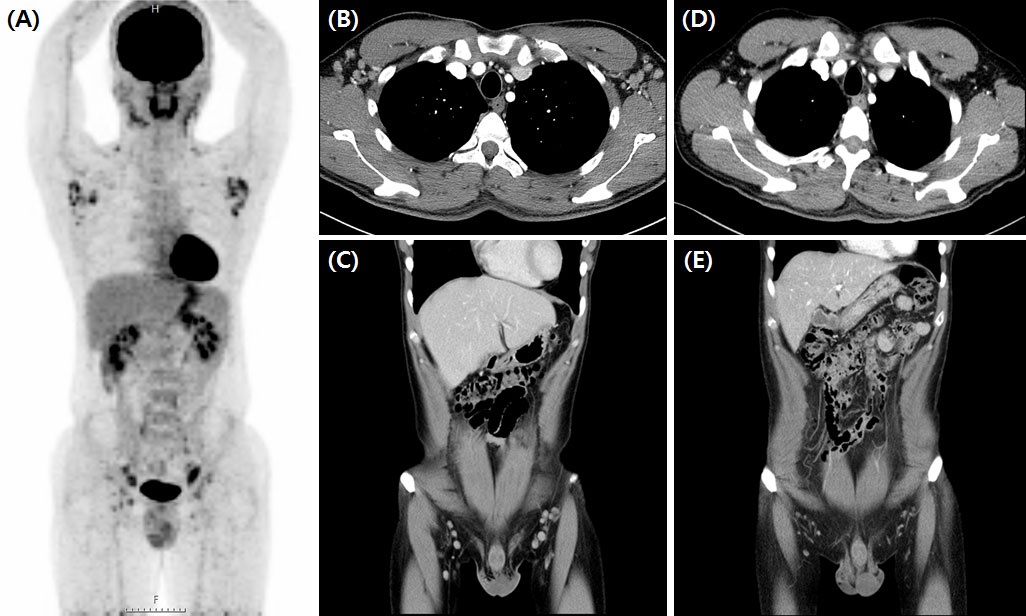

FIGURE 3

www.frontiersin.org

Figure 3 Significant regression of enlarged lymph nodes after third siltuximab infusion. Initial FDG-PET CT scan of iMCD plasma cell type patient (A) showed MCD involving bilateral cervical, supraclavicular, axillae, common and external iliac, and inguinal lymph nodes. CT scan findings before (B, C) and after (D, E) siltuximab infusion showed markedly regressed MCD-involved lymph nodes in the bilateral inguinal and axillar areas. FDG-PET CT, 18-fluoro-2-deoxy-D-glucose positron emission tomography-computed tomography; iMCD, idiopathic multicentric Castleman disease.

Siltuximab treatment, an anti-IL-6 therapy used to treat MCD in patients negative for HIV and HHV-8 and proven to improve clinical outcomes, was used in patients with MCD exhibiting systemic symptoms and laboratory abnormalities. Among them, 55.6% (n=15) were treated with siltuximab as first-line therapy and 44.4% (n=12) were treated as second-line therapy after previous CHOP chemotherapy (n=7) or steroid pulse therapy (n=5). CR was observed in 22 (81.5%) patients, and a durable symptomatic response was achieved at a median of 23.5 days (range, 15–82 days) after the initiation of siltuximab treatment. On laboratory evaluation after three months of treatment, the median values of hemoglobin (range, 10.4–12.6 g/dL; p<0.001), CRP (range, 6.31–2.15 mg/dL, p=0.002), ESR (range, 62.4–17.1 mm/h; p<0.001), serum total protein (range, 8.2–7.4 g/dL; p=0.004), and serum albumin (range, 3.1–3.9 g/dL; p<0.01) were significantly improved (Figure 2). One patient demonstrated a dramatic regression of multifocal lymphadenopathies in imaging studies after the third siltuximab infusion (Figure 3). At a median of 12.9 months (range, 5.5–93.0 months) after the initiation of siltuximab, 66.7% (n=18) and 14.8% (n=4) of patients achieved CR and PR, respectively. Of the siltuximab responders who achieved CR or PR (81.5%), all achieved CR in terms of clinical symptoms and laboratory parameters before the radiologic response. However, five patients (18.5%) did not show a proper response during siltuximab treatment, and three had systemic symptoms, abnormalities in laboratory markers, and unresponsive multiple lymphadenopathies despite siltuximab infusion. The remaining two patients discontinued treatment with siltuximab with SD. One patient refused treatment due to poor general condition after the second cycle of siltuximab, and the other patient changed treatment to CHOP chemotherapy for faster resolution of the lymphoproliferative mass compressing the right ureter despite significant symptomatic improvement after four cycles of siltuximab. On average, improvements in clinical symptoms, laboratory parameters, and radiologic parameters of MCD among responders were observed after one, three, and 18 cycles of siltuximab treatment, respectively. The clinical responses of siltuximab-treated patients with MCD (n=27) are presented in Table 3.